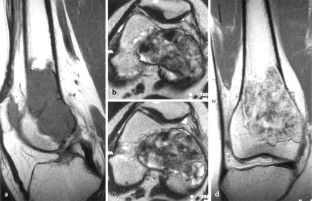

MRI morphology of bone tumors and tumor-like lesions

Für das Staging und die Charakterisierung von Knochentumoren und tumorähnlichen Läsionen ist in der Magnetresonanztomographie (MRT) der Einsatz von Spinechosequenzen erforderlich. Die MRT hat nur einen geringen Stellenwert in der Bestimmung der Dignität. Obwohl viele Knochentumoren und tumorähnliche Läsionen eine vergleichbare Morphologie in dieser bildgebenden Modalität aufweisen, können einige Tumorentitäten mittels MRT recht zuverlässig diagnostiziert werden. Hierzu zählen Knorpeltumoren, die solitäre und aneurysmatische Knochenzyste, der Riesenzelltumor, fetthaltige Läsionen und bis zu einem gewissen Grad auch das Osteoidosteom und das Osteoblastom. Es werden praktische Tipps gegeben, wann bei Tumorverdacht die MRT eingesetzt werden sollte, wie bei einem zufällig bei einer MRT gefundenen Tumor die Untersuchung modifiziert werden sollte und welcher Tumor vorliegen könnte.

Spin-echo sequences are mandatory at MRI for staging and characterization of bone tumors and tumor-like lesions. MRI is of minor value in the estimation of the malignant potential of an osseous lesion. Although many bone tumors and tumor-like lesions present similar morphology at MRI, some entities can be diagnosed with good reliability. These include chondrogenic tumors, solitary and aneurysmal bone cysts, giant cell tumors, lesions containing fatty tissue and, to a certain extent, osteoid-osteomas and osteoblastomas. Practical advice is given regarding when to perform a MRI study in cases of tumor suspicion. Further advices are given for cases a tumor is found incidentally at a MRI study, how to modify the study and which kind of tumor may be present.